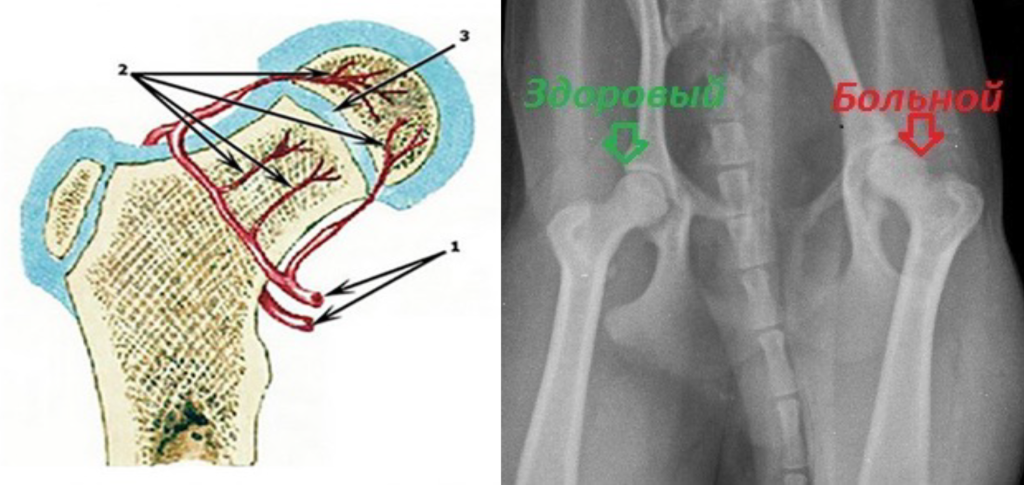

Болезнь Пертеса (Легга-Кальве-Пертеса) — это патология, при которой нарушается кровоснабжение головки бедренной кости, что приводит к ее некрозу (отмиранию) и разрушению. Чаще всего болезнь встречается у собак карликовых и мелких пород (той-терьеры, йорки, шпицы, чихуахуа, таксы, карликовый пудель), но может наблюдаться и у кошек.

- Рентген тазобедренного сустава (на снимке заметны изменения формы головки бедра).